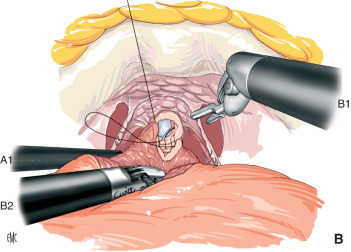

PROSTATECTOMIA ROBÓTICA

A PROSTATECTOMIA ROBÓTICA é uma técnica moderna e minimamente invasiva que utiliza uma plataforma robótica para melhorar a qualidade e precisão da cirurgia